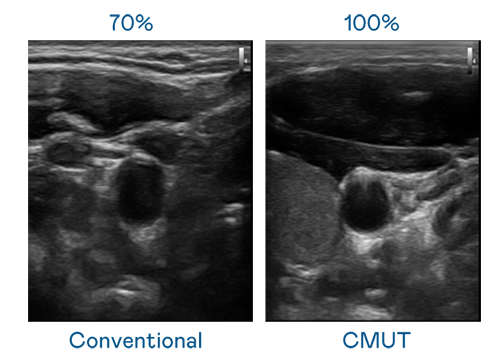

CMUT 技术是一种用电容式微机电元件来产生超音波讯号的技术。与传统 PZT 压电式技术相比,CMUT 频宽增加 30%,更宽频的超音波讯号让影像解析度大幅提升,是实现高影像品质医疗超音波扫描、促进精准医疗发展的关键技术。

大频宽带来超清晰影像

超音波影像的解析度高低,首先取决于探头能发出的讯号频宽。九游会·AG CMUT 可提供高清晰的超音波讯号,提供高频宽、高灵敏度、影像纹理细节更高的超音波影像,协助医护人员缩短影像判读时间及利用精准的医疗影像进行诊断。